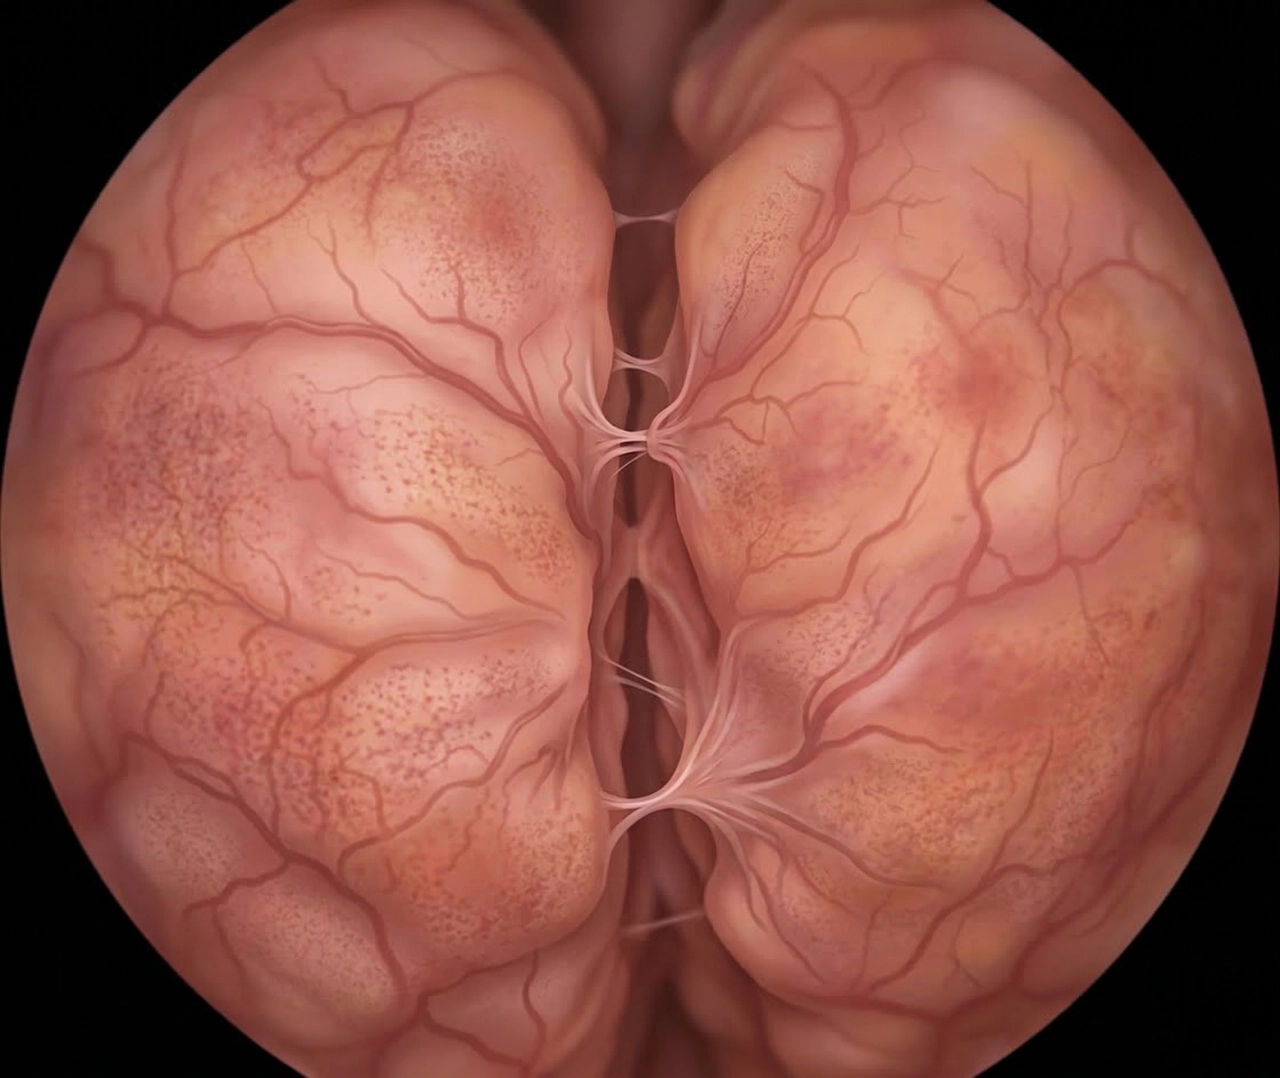

전립선 비대증이 생기는 과정

ZAII UROLOGY HOSPITAL